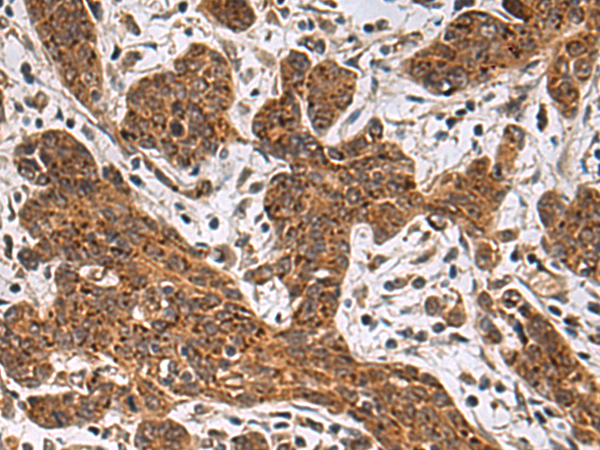

分类: 科研抗体货号: P11855别名: IMPD; RP10; IMPD1; LCA11; sWSS2608应用: WB,IHC反应种属: Human, Mouse, Rat